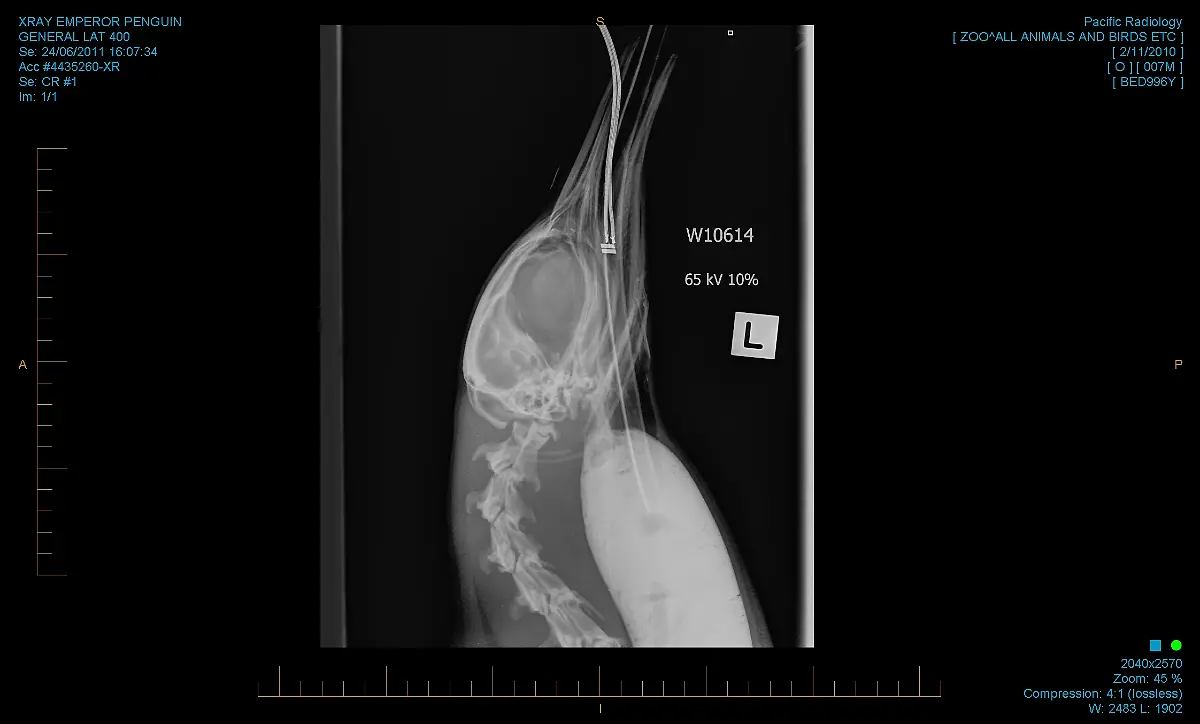

3000 Kilometer von seiner Heimat entfernt taucht ein Pinguin an der Küste Neuseelands auf. Die neue Umgebung bekommt "Happy Feet" nicht. Er ist überhitzt, ausgemergelt und hat Sand im Magen. In einer dramatischen Rettungsaktion kommt er in den Zoo Wellington, wo Ärzte um sein Leben kämpfen.